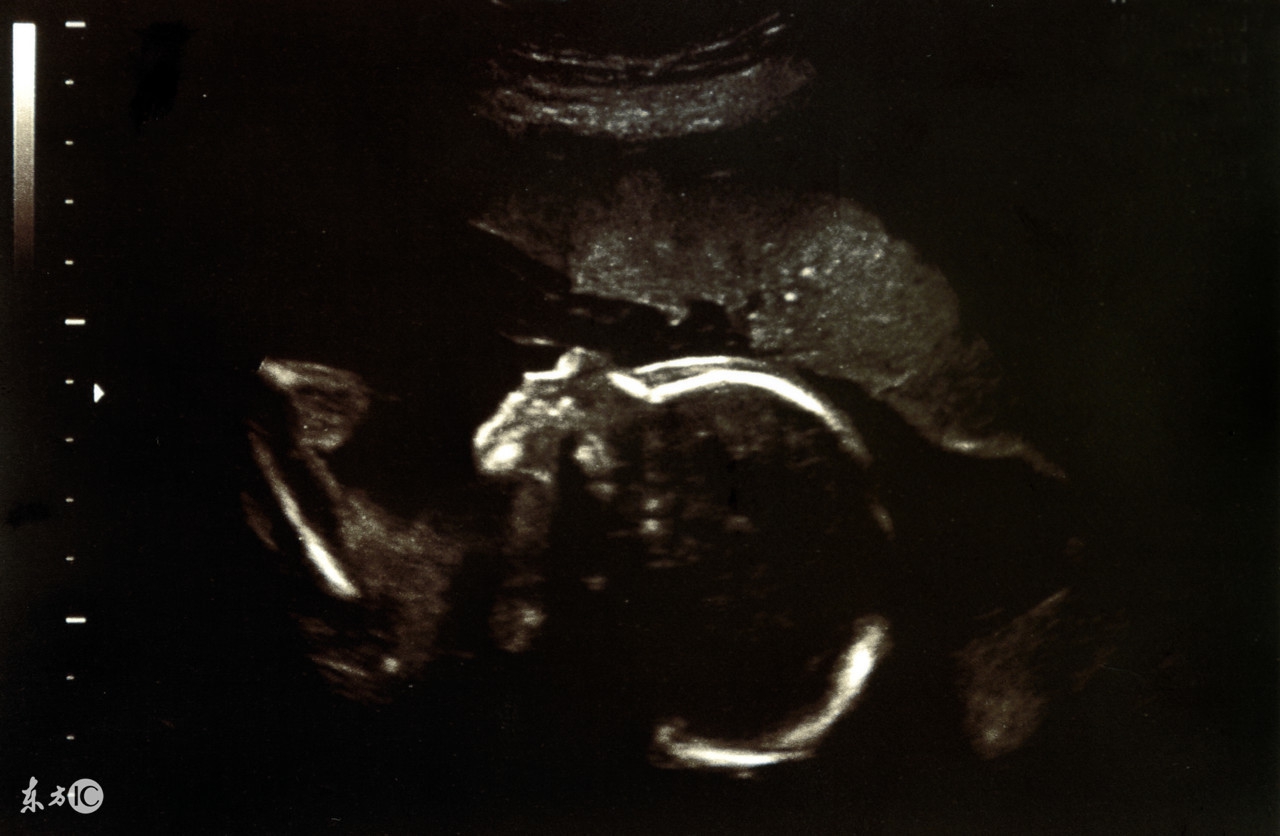

还有的妇女怀上葡萄胎后,腹部异常的增大,肚子看起来要比正常孕周大得多,有的人甚至误以为自己是怀上的双胞胎或者多胞胎,殊不知却是空欢喜一场。同时因为怀的是葡萄胎,那么它就不具备正常胎儿所应有的一些表现,比如在怀孕五个月的时候孕妈妈一般能感受到腹中小宝宝在动,但如果怀上的是葡萄胎的话,那么就感受不到胎儿活动了,超声检查下也看不到胎动。B超检查和测定绒毛膜促性腺激素(血β-HCG)可以帮助诊断,当怀的是葡萄胎时,我们在B超下看不到正常胎儿的形态,而是出现雪片状或蜂窝状的图片,血β-HCG在葡萄胎时测出的数值会比正常妊娠高出很多。